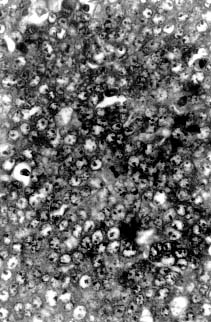

| Fig. 1. Large areas of necrosis scattered throughout the tumor forming lobules surrounded by well-defined fibrous strands. 62.5 x, H&E. | Fig. 2. Mitotic figures observed at high power field. 500 x H&E. |

Microscopically, the mass was composed of closely packed ribbons and nests of large round to polygonal cells with low amounts of basophilic cytoplasm and large round nuclei with prominent nucleoli divided into demarcated lobules by delicate septa of fibrous tissue. Large areas of necrosis werescattered throughout the mass forming lobules surrounded by well-defined fibrous strands (Fig. 2). The morphology of the tumor cells was consistent with a seminoma. In addition, clusters of small round to oval eosinophilic cells with condensed round nuclei were observed occasionally in the middle of some lobules. A minimum amount of hemorrhage was also observed.